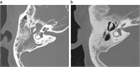

1. 診断の基本:鼓膜所見による診断が基本であり、必要に応じて側頭骨CTで含気化や陰影を確認する。中耳真珠腫疑い例ではMRIが有用である(推奨度1、RJ)